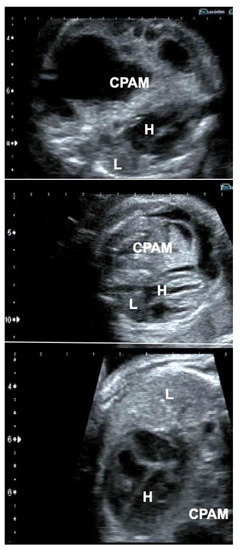

Following long-standing compression of the ipsilateral and contralateral lung tissue by very large CPAMs—even after technically successful interventions—some lungs do not distend and do not exhibit improved perfusion and are considered too small or too dysfunctional for postnatal survival. As mentioned previously, fetoscopic tracheal balloon occlusion (FETO) may serve as the last resort to achieve lifesaving lung catch-up growth in these cases (Figure 6).

Figure 6.

Effect of FETO in a fetus with a giant congenital pulmonary airway malformation (CPAM) (top), whose lungs did not distend—despite several previous interventions—after long-standing compression and were considered too small or too dysfunctional for postnatal survival (middle). In this case, FETO at 30 + 4 weeks of gestation served as the last resort to achieve lifesaving lung catch-up growth (bottom). H = heart; L = lung.